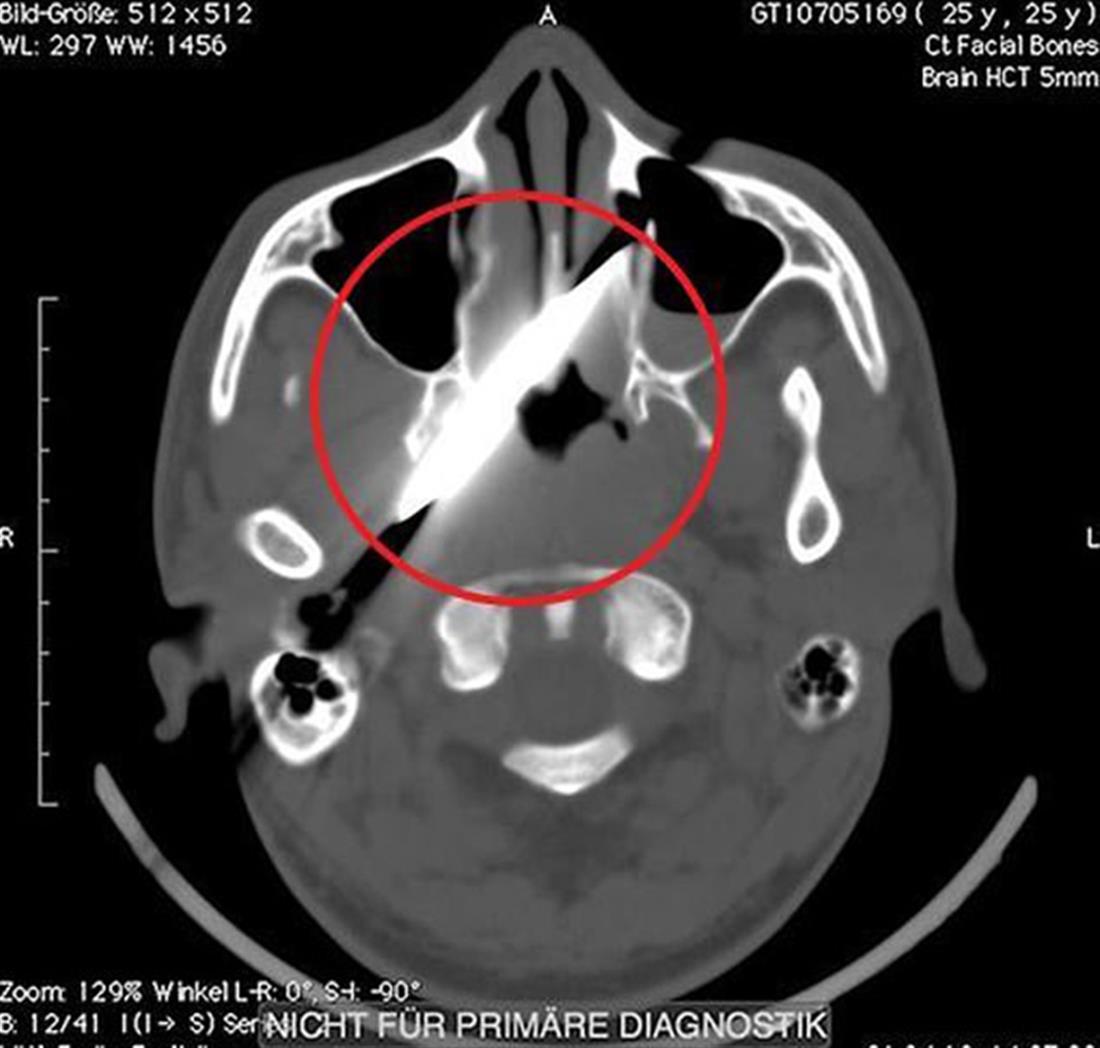

Συγκλονίζει η ακτινογραφία του κεφαλιού ενός άνδρα πάνω στο οποίο ήταν καρφωμένο ένα μαχαίρι μήκους 10 εκατοστών, τέσσερις μέρες αφού δέχθηκε μαχαιριά!

Σύμφωνα με τους θεράποντες ιατρούς, η λεπίδα μπήκε κάτω από το μάτι του και έμεινε εκεί λόγω του ότι «σκάλωσε» στο κόκκαλό του.

Οι γιατροί δημοσίευσαν τις ακτινογραφίες, εξαιτίας του πρωτοφανούς γεγονότος.

Χρειάστηκαν πάνω από δύο μέρες μέχρι να μπορέσει να κάνει αγγειογραφία, η οποία έδειξε ότι δεν είχε υποστεί τραυματισμό στα νεύρα του και στη συνέχεια μπήκε στο χειρουργείο, όπου του αφαιρέθηκε ολόκληρο το μαχαίρι.